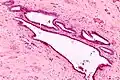

Endosalpingiosis is diagnosed by a pathologist on excision (e.g. biopsy).

It is characterized by cysts with tubal-type epithelium (e.g. ciliated epithelium) surrounded by a fibrous stroma. It is not often associated with hemorrhage.

Intermed. mag.